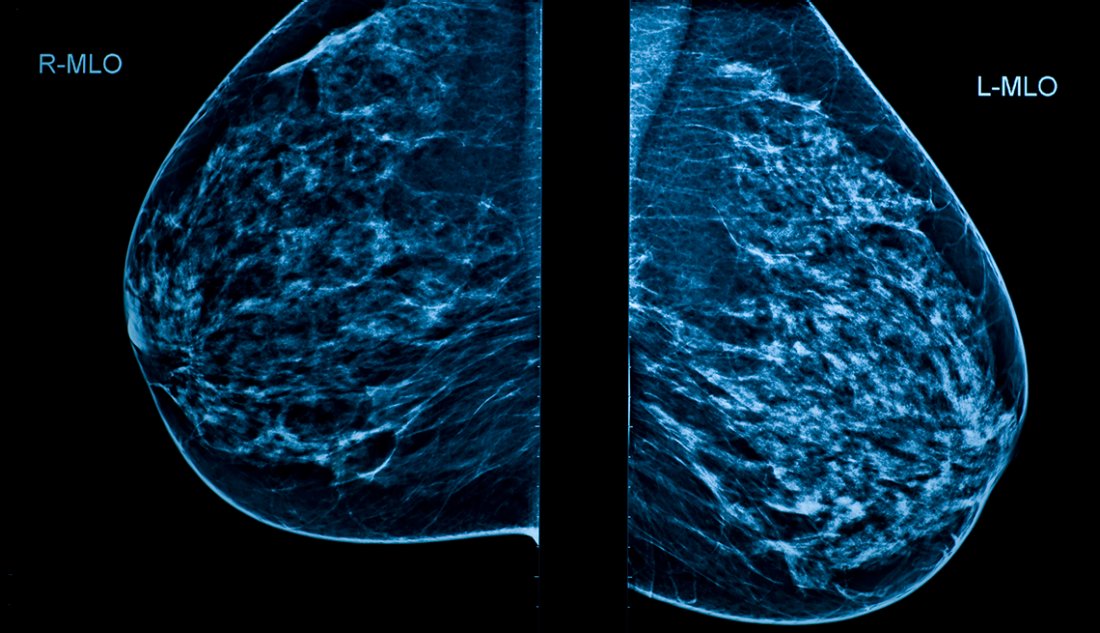

La mamografía es un tipo específico de imagen que utiliza un sistema de rayos X de baja dosis para examinar sus senos. Este examen se llama mamografía y se usa como una herramienta de detección para detectar el cáncer de mama temprano en mujeres que no tienen síntomas y para detectar y diagnosticar enfermedades de las mamas en aquellas que experimentan síntomas como un bulto, dolor o secreción del pezón.

La mamografía 3D es una mamografía que consiste en múltiples imágenes de los senos tomadas en segundos para producir una imagen 3D. El radiólogo mira a través del tejido mamario una capa delgada a la vez, para que los detalles finos sean más visibles. Los pacientes tienen la opción de elegir una mamografía 2D o una 3D.